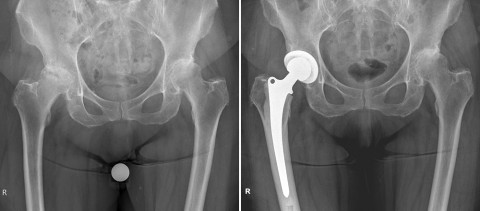

Fall 4: 82-jährige Patientin mit einer schweren Arthrose der rechten Hüfte

Auch hier zeigte sich wie in Fall 3 eine durchblutungsbedingte Schwächung des Knochens. Aufgrund der verringerten Knochendichte (Osteoporose) wurde die Patientin in Hybrid-Technik versorgt: Die Pfannenkomponente wurde zementfrei eingebracht, der Femurschaft wurde in zementierter Technik im Oberschenkel verankert. Die Operation wurde in minimalinvasiver Technik durchgeführt, die Mobilisation konnte mit vollem Körpergewicht erfolgen.